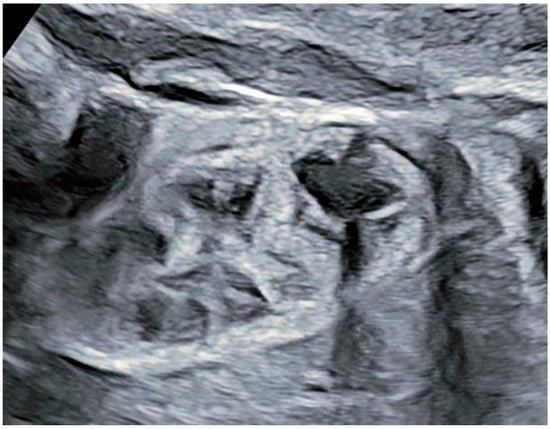

2. Case Presentation

Patient Information